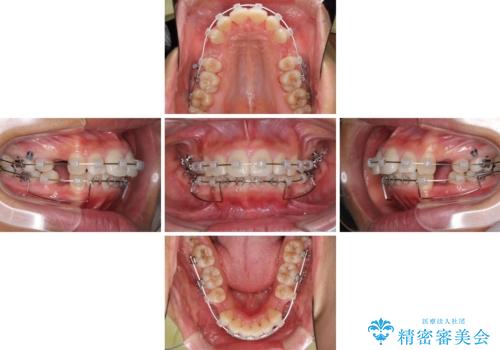

- クリアブラケット

途中で来院されない時期があったため、期間が長引き、更には磨き残しが多かったことで虫歯が多く発現してしまいました。

しっかりと通院するようになってからは順調に治療が進み、横顔の印象が変わるほどスッキリとした口元となりました。